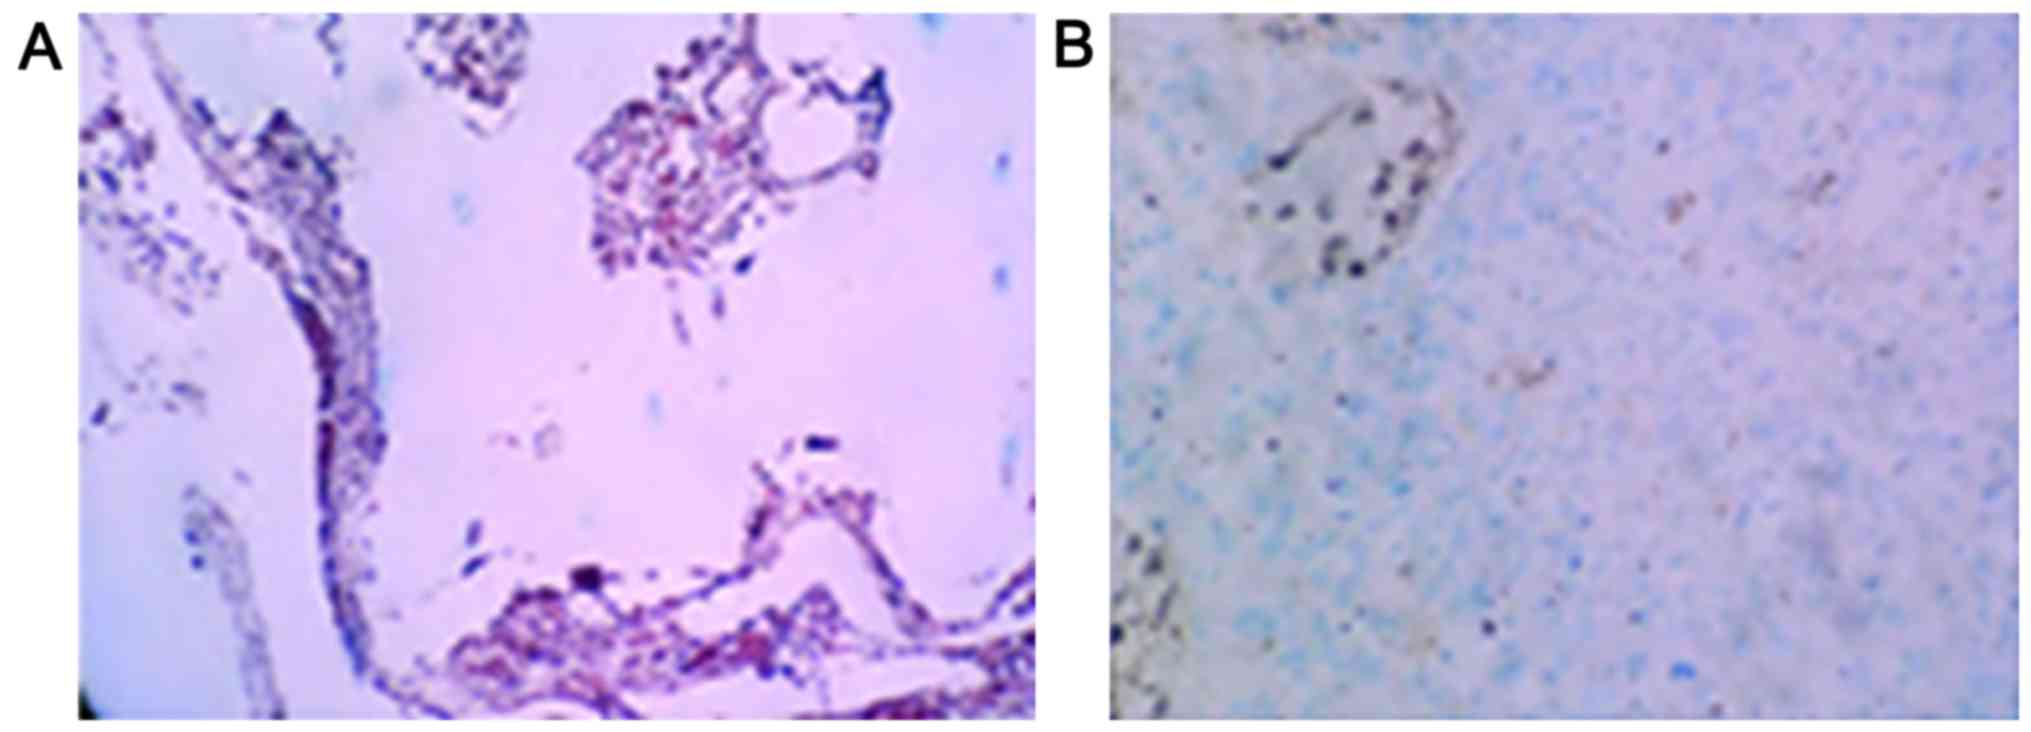

Immunohistochemical staining evaluation

criteria

Ten casual fields of view were observed under

microscopy, with yellow or brown particles in the nuclei or

cytoplasm with clear backgrounds being considered as positive

staining. In addition, samples showing positive staining were

divided into strong staining (>95% positive cells), moderate

staining (51–95% positive cells), weak staining (2–50% positive

cells), and absence of expression (<2% positive cells)

categories (5). In this study, weak

staining and absence of expression were interpreted as negative

expression, and strong staining and moderate staining as positive

expression.

Positive staining for p-AKT and HSP70 proteins

manifested as purple particles in the cytoplasm (Figs. 4 and 5).